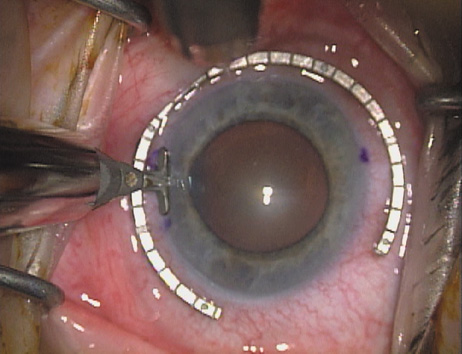

Case 2 is a 79-year-old woman who presented with a very dense left cataract. Her refraction was recorded at −2.25 +2.75 × 125 with a difficult end point. Her manual keratometry and topography measurements were consistent and revealed slightly less than 1.75 D at 120 degrees. Because of the questionable refraction, greater value was placed on the corneal measurements. Based upon the cataract nomogram, the plan was for paired LRIs of 40 degrees to be placed over the steep 120-degree axis (Figs. 1219).

Fig. 12. In this left eye, the steep meridian is at the 120-degree axis and has been delineated by opposing limbal marks. The upper left hand ink mark represents the 6:00 position for orientation. (Reprinted from Hardten DR, Lindstrom RL, Davis EA. Phakic Intraocular Lenses: Principles and Practice. Thorofare, NJ: SLACK Incorporated, 2004, with permission.)

Fig. 13. The incision is begun 20-degrees to one side of the centering mark. (Reprinted from Hardten DR, Lindstrom RL, Davis EA. Phakic Intraocular Lenses: Principles and Practice. Thorofare, NJ: SLACK Incorporated, 2004, with permission.)